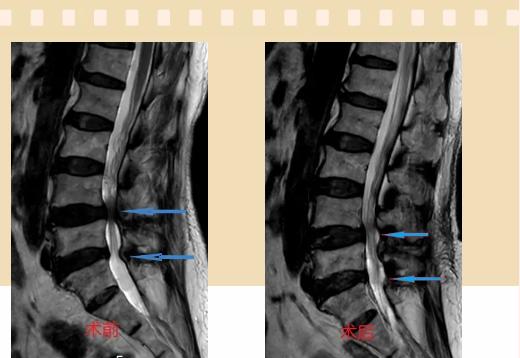

入院后李鵬副主任醫(yī)師為其進(jìn)行了詳細(xì)的查體,完善了術(shù)前的檢查,明確診斷為:腰椎管狹窄癥(L4/5、L5/S1),病人合并2型糖尿病,請(qǐng)內(nèi)分泌科會(huì)診,穩(wěn)定血糖后,麻醉科會(huì)診病人,排除手術(shù)禁忌,李鵬為病人制定了手術(shù)方案:?jiǎn)蝹?cè)入路雙側(cè)減壓(ULBD)。

手術(shù)采用三個(gè)微創(chuàng)小切口,兩個(gè)節(jié)段減壓手術(shù)時(shí)間2.5小時(shí),出血50ml。術(shù)后2天腰圍保護(hù)下床活動(dòng),術(shù)后5天順利出院。

傳統(tǒng)腰椎管狹窄癥的手術(shù)治療,往往需要切開減壓,同時(shí)需要內(nèi)固定融合術(shù),創(chuàng)傷很大,同時(shí)可能需要輸血,臥床時(shí)間較長(zhǎng),病人合并糖尿病,感染風(fēng)險(xiǎn)也高,而本次采用的UBE-ULBD手術(shù)切口更?。悠饋?lái)約3cm,如果是單節(jié)段狹窄只需要不到2cm切口)、創(chuàng)傷更小,術(shù)后恢復(fù)較快,可以更早地恢復(fù)正?;顒?dòng)。

此外,手術(shù)保留了病變節(jié)段的穩(wěn)定性,是一種微創(chuàng)的椎管減壓手術(shù),能通過(guò)切除部分椎板、關(guān)節(jié)突關(guān)節(jié)、黃韌帶來(lái)解除神經(jīng)根和硬膜囊的壓迫,不需要額外行腰椎內(nèi)固定術(shù),不需要螺釘及融合器的植入,病人術(shù)后腰椎的活動(dòng)度不受影響。(盧   闖  劉   旭   袁錦鈺)